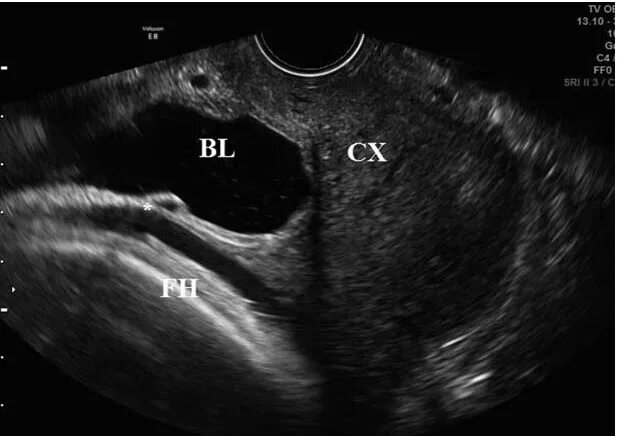

Оценка рубца на матке после кесарева сечения. рубец на матке норма. рубец на матке после кесарева сечения толщина норма. нормальная толщина рубца на матке после кесарева.Состоятельность рубца на матке после кесарево узи. узи рубца на матке при беременности. рубец на матке после кесарево узи. несостоятельный рубец на матке узи.Критерии несостоятельности рубца на матке. толщина рубца на матке после кесарева. локализация рубца на матке. рубец на матке норма.Узи несостоятельность рубца на матке. по узи несостоятельность рубца после кесарева сечения. состоятельность послеоперационного рубца на матке узи. несостоятельность рубца на матке после кесарева узи.Узи несостоятельность рубца на матке. узи матки после кесарева сечения. рубец после миомэктомии узи.Узи критерии несостоятельного рубца. критерии несостоятельности рубца на матке. несостоятельность рубца на матке. признаки несостоятельности рубца на матке.Аденомиоз рубца на матке после кесарева. эндометриоз кожного рубца узи. эндометриоз по рубца узи.Несостоятельность рубца на матке после кесарева сечения. критерии несостоятельности рубца на матке. состоятельность рубца на матке после кесарева. несостоятельность шва на матке.Ведение беременной с рубцом на матке. ведение родов у женщин с рубцом на матке. оценка состояния рубца на матке. критерии состоятельности рубца на матке.Показания к операции кесарево сечение при тазовом предлежании плода. показания к кесареву сечению при тазовом предлежании. показания к операции кесарево сечение при тазовом предлежании. толщина рубца на матке после кесарева норма.Узи рубца на матке при беременности. рубец на матке после кесарево узи. узи матки после кесарева сечения.Узи несостоятельность рубца на матке. несостоятельный рубец на матке узи. несостоятельность рубца на матке после кесарева сечения узи. толщина рубца на матке на узи.Рубец от кесарева на узи.Состоятельность рубца на матке. неполноценность рубца на матке.Полноценный рубец на матке. расхождение рубца на матке при беременности. послеоперационный рубец на матке норма. несостоятельность рубца на матке мрт.Толщина рубца на матке 5.2. критерии несостоятельности рубца на матке. рубец после кесарева сечения норма по узи. несостоятельность послеоперационного рубца на матке по узи.Рубец на матке после кесарева сечения толщина норма. измерение рубца на матке по узи. узи несостоятельность рубца на матке. рубец на матке после кесарева сечения по узи.Рубец на матке на узи описание. узи несостоятельность рубца на матке. узи рубца на матке при беременности. несостоятельность шва после кесарева сечения на узи.Врастание плаценты на узи. врастание плаценты в рубец на матке узи. эхограмма врастания плаценты. врастание плаценты в рубец на матке.Критерии несостоятельности рубца на матке. рубец матки после операции. локализация рубца на матке.Рубец на матке 1 1Узи послеоперационного рубца. несостоятельность послеоперационного рубца. несостоятельный рубец на матке узи.Нормальная толщина рубца на матке после кесарева сечения. толщина рубца на матке при беременности норма. норма толщина рубца на матке. норма толщины рубца на матке по неделям беременности после кесарева.Рубец на матке 1 1Признаки несостоятельности рубца. несостоятельность рубца на матке. симптомы несостоятельности рубца на матке. критерии несостоятельности рубца на матке.Несостоятельность шва после кесарева сечения на узи. несостоятельный рубец на матке узи. узи несостоятельность рубца на матке.Узи несостоятельность рубца на матке. несостоятельность рубца на матке после кесарева сечения узи. рубец на матке на узи описание. несостоятельность шва после кесарева сечения на узи.Ультразвуковым признаком врастания плаценты является. врастание плаценты в рубец форум.Узи состоятельный рубец на матке. узи несостоятельность рубца на матке. узи рубца на матке при беременности.Рубец на матке после кесарева сечения узи.Несостоятельность рубца на матке после кесарева. несостоятельность рубца на матке после кесарева по узи. локализация рубца на матке после кесарева сечения. нормы рубца на матке после кесарева сечения.Несостоятельность рубца узи. узи несостоятельность рубца на матке. по узи несостоятельность рубца после кесарева сечения. несостоятельность рубца на матке после кесарева по узи.Презентация рубец на матке. рубец на матке мкб 10 код. мкб несостоятельность рубца на матке после кесарева. диагноз рубец на матке.Узи несостоятельность рубца на матке. узи рубца на матке после кесарева.Рубец на матке после кесарево узи. толщина рубца на матке на узи. беременность в рубце на матке узи.Несостоятельность рубца на матке после кесарева по узи. несостоятельность рубца на матке после кесарева узи. несостоятельность послеоперационного рубца.Несостоятельность рубца на матке после кесарева узи. несостоятельность шва после кесарева сечения на узи.Узи после кесарева сечения. шов на матке после кесарева заключение узи.Нормы рубца на матке после кесарева сечения. нормальная толщина рубца на матке после кесарева сечения. рубец на матке при беременности норма. норма толщины рубца на матке по неделям беременности.Рубец на матке 1 1